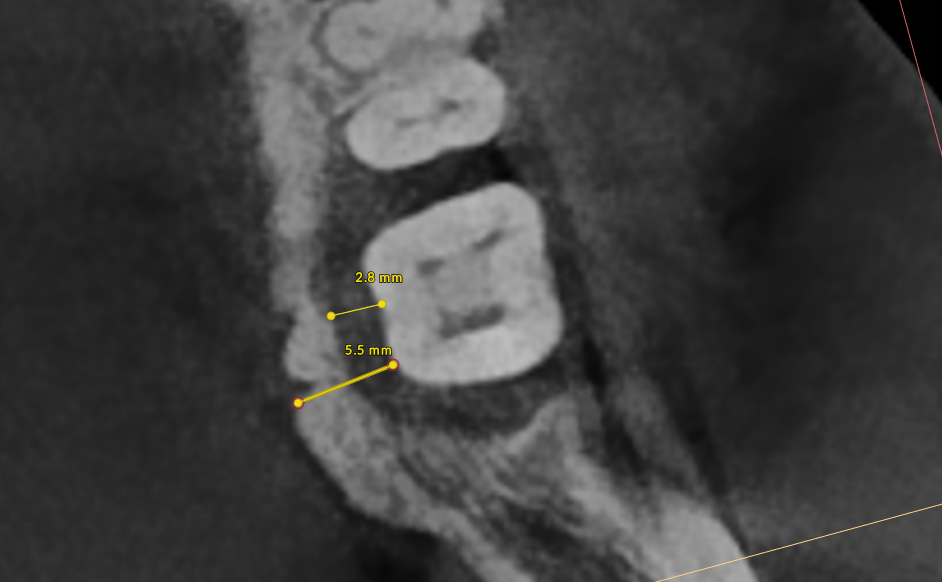

Bone thickness and shape: Bacteria on your teeth can only cause bone destruction within about 1.5 mm of where they sit, referred to as their "sphere of influence." When the surrounding bone is thin or roots are very close together, bacteria can destroy the bone completely, leading to gum recession and more exposed tooth surface. In these cases, non-surgical therapy is often sufficient. When bone is thick, bacteria can only destroy part of it, creating craters or "moats" around the tooth. These craters cannot be fully cleaned with non-surgical treatment and typically require surgery to correct.

- X-Rays (Radiographs): X-rays show the pattern and extent of bone loss. We can see whether bone has been lost evenly (horizontal loss) or whether craters and vertical defects have formed. This pattern directly determines which type of treatment you need.

Step 4, Osseous Surgery (if needed): For pockets that remain deep, surgery gives us direct access to clean root surfaces and reshape or rebuild bone.